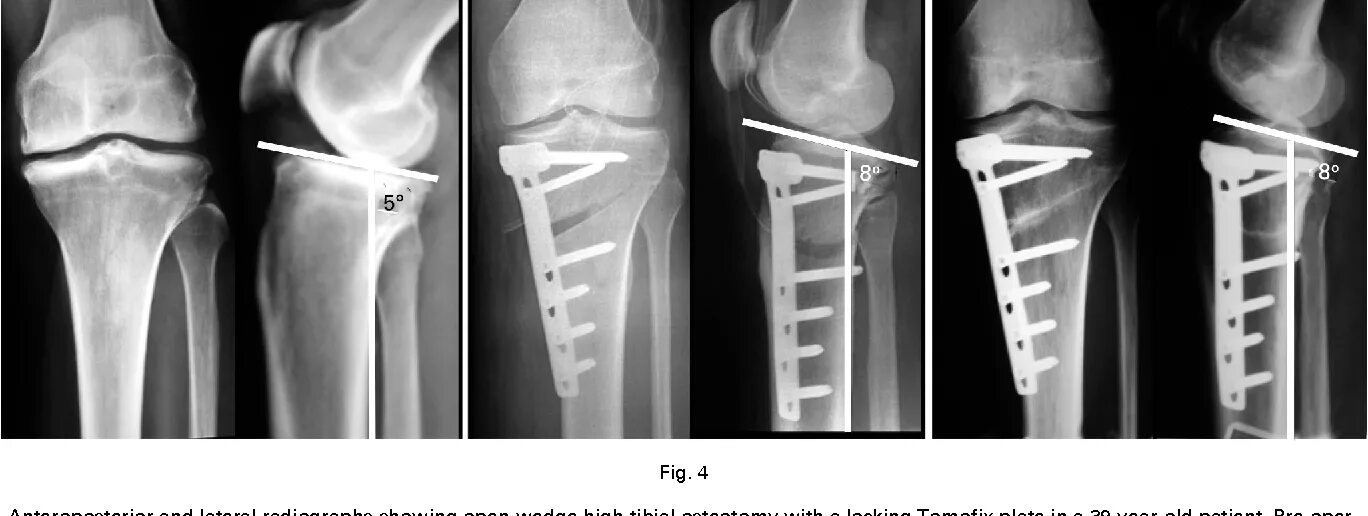

Пяточная остеотомия